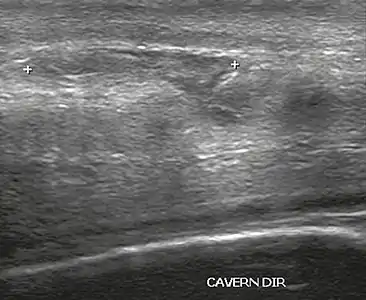

Ultrasound examination is able to depict the tunica albuginea tear in the majority of cases (as a hypoechoic discontinuity in the normally echogenic tunica). In a study on 25 patients, Zare Mehrjardi et al. concluded that ultrasound is unable to find the tear just when it is located at the penile base. In their study magnetic resonance imaging (MRI) accurately diagnosed all of the tears (as a discontinuity in the normally low signal tunica on both T1- and T2-weighted sequences). They concluded that ultrasound should be considered as the initial imaging method, and MRI can be helpful in cases that ultrasound does not depict any tear but clinical suspicions for fracture are still high. In the same study, authors investigated accuracy of ultrasound and MRI for determining the tear location (mapping of fracture) in order to perform a tailored surgical repair. MRI was more accurate than ultrasound for this purpose, but ultrasound mapping was well correlated with surgical results in cases where the tear was clearly visualized on ultrasound exam.[10] The advantage of ultrasound in the diagnosis of penile fracture is unrivaled when its noninvasive, cost-effective, and nonionising nature are considered.[11]

In the ultrasound examination, a lesion of the tunica albuginea presents as an interruption in (loss of continuity of) the echoic line representing it (Figure 4). Small, moderate, or broad hematomas demonstrate the extent of that discontinuity. Intracavernous hematomas, sometimes without the presence of a tunica albuginea fracture, can be observed when there is a lesion of the smooth muscle of the trabeculae surrounding the sinusoid spaces or the subtunical venular plexus.[2]

In 10–15% of penile traumas, there can be an accompanying urethral lesion. When blood is observed in the urethral meatus, contrast-enhanced evaluation of the urethra is necessary. In cases in which the ultrasound findings are inconclusive, the use of magnetic resonance imaging can facilitate the diagnosis and is recommended by various authors.[2]